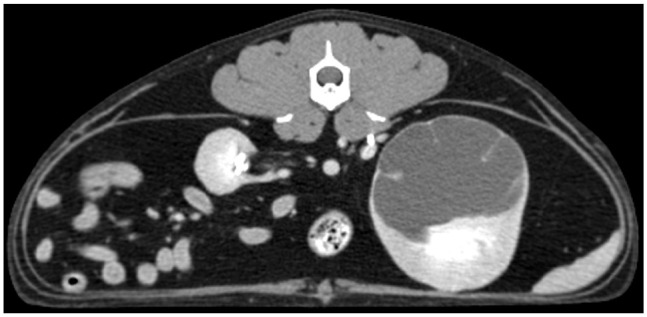

病例摘要:患者是一只 5.5 岁的雄性阉割短毛猫,两年前开始出现进行性慢性肾病。腹部超声波检查发现双侧慢性肾脏变性、肾结石、皮质高回声和梗死。使用 Synovis 血管耦合系统对肾动脉和静脉进行端对端吻合,进行了左侧正位肾移植。移植两个月后,肾脏数值升高,腹部超声波检查发现移植肾肾积水和肾积脓。透视前行肾盂造影发现近端输尿管狭窄。对其进行了近端新输尿管囊肿切除术,术后肾脏数值恢复正常。12 个月后,该猫因急性绞窄尿和严重氮质血症接受了重新评估。对比增强 CT 显示移植肾出现严重肾积水,近端输尿管阻塞,膀胱粘连。经探查发现,腹膜后纤维化覆盖了移植肾。考虑到临床情况,患者被放置了皮下输尿管旁路装置(SUB)。每隔 1-3 个月对临床病理分析、环孢素谷值、需氧尿培养和移植肾的超声波评估进行一次监测。每 3-6 个月重新评估一次 SUB 的通畅性。放置 SUB 15 个月后,由于膀胱造口导管扭结,SUB 出现闭塞,因此进行了更换。放置 SUB 后 28 个月,该猫的肾功能和临床状况恶化,最终安乐死:据作者所知,这是首次报道使用 SUB 装置治疗猫移植肾的输尿管梗阻。

Case summary: A 5.5-year-old male neutered domestic shorthair cat was presented with a 2-year history of progressive chronic kidney disease. Abdominal ultrasonography revealed bilateral chronic renal degeneration, nephrolithiasis, cortical hyperechogenicity and infarction. Left orthotopic renal transplantation was performed using the Synovis vascular coupling system for end-to-end anastomosis of the renal arteries and veins. Two months after transplantation, renal values were elevated, and abdominal ultrasonography revealed hydronephrosis and hydroureter of the transplanted kidney. Fluoroscopic antegrade pyelography identified a proximal ureteral stricture. Proximal neoureterocystostomy was performed and renal values normalized postoperatively. The cat was re-evaluated for acute stranguria and severe azotemia 12 months later. Contrast-enhanced CT revealed severe hydronephrosis of the transplanted kidney, obstruction of the proximal ureter and adhesions to the urinary bladder. Upon exploration, retroperitoneal fibrosis was found covering the transplanted kidney. Given the clinical situation, a subcutaneous ureteral bypass device (SUB) was placed. Clinicopathologic analyses, trough cyclosporine levels, aerobic urine cultures and ultrasonographic evaluations of the transplanted kidney were monitored every 1-3 months. Patency of the SUB was reassessed every 3-6 months. At 15 months after placement, the SUB occluded due to kinking of the cystostomy catheter and was replaced. At 28 months after SUB placement, renal function and clinical status deteriorated, and the cat was euthanized.